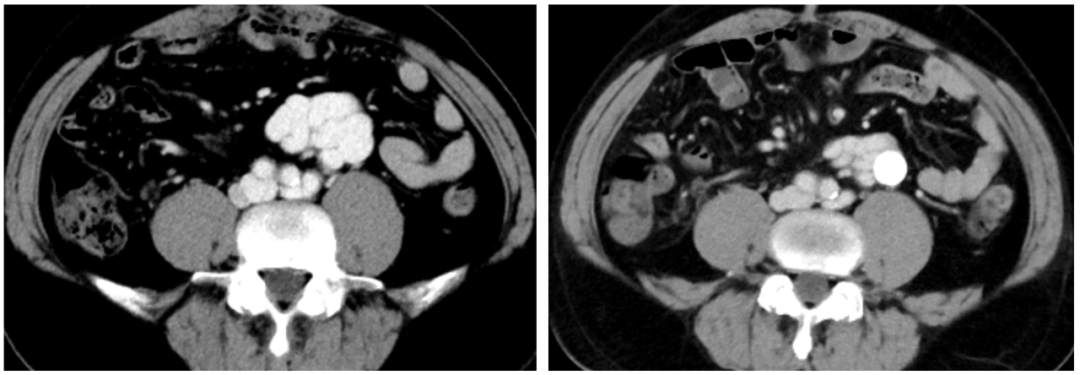

2)腹部增強CT

異常分流道曲張靜脈較前顯著萎縮

術(shù)后患者的肝臟血管超聲提示患者原本的離肝血流已逆轉(zhuǎn)為向肝血流,1月后的CT復查顯示門靜脈較術(shù)前的纖細狀態(tài)已得到明顯恢復,間接證實TIPS分流并未進一步降低患者的肝臟灌注,其隨訪至今也未在發(fā)生肝性腦病。對于自發(fā)性門體分流所致的反復肝性腦病患者,相信TIPS+異常分流道近端栓塞是值得進一步探索研究的治療方法。需臨床進一步驗證。